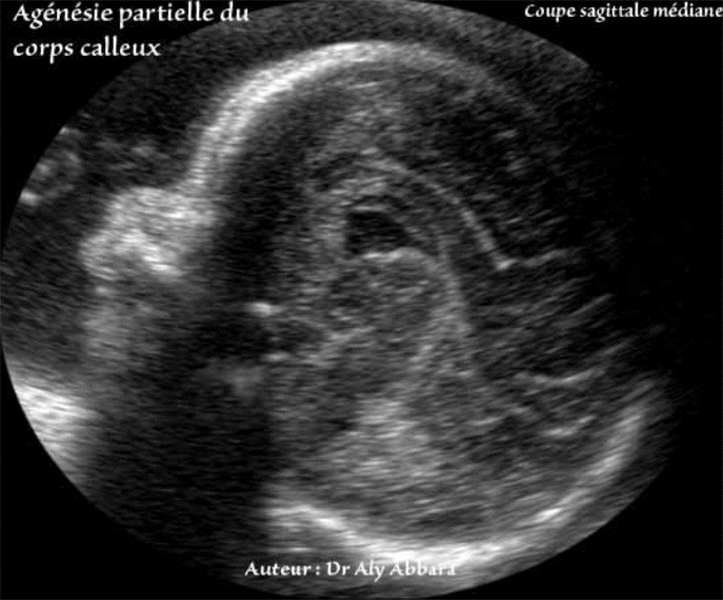

Agenesie Du Corps Calleux Description Anatomique Signes Echographiques In Utero